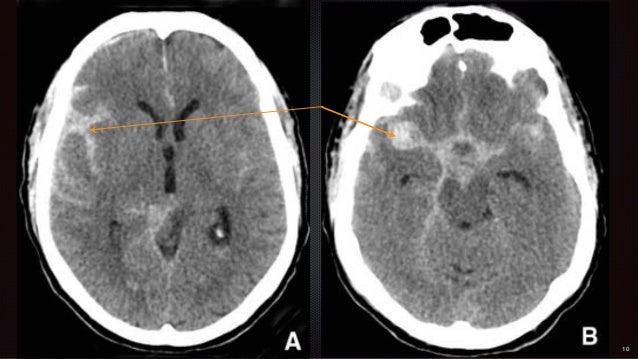

Investigations Devant toute suspicion d'hémorragie sousarachnoïdienne, un CTscan natif doit être réalisé Il permet d'établir le diagnostic lorsqu'il montre la présence de sang sousarachnoïdien, détecte d'éventuelles autres lésions responsables de la symptomatologie et constitue un examen rapide, peu invasif et disponible en permanence dans la plupart des hôpitaux régionaux. HEMORRAGIE SOUS ARACHNOÏDIENNE (HEMORRAGIE MENINGEENON TRAUMATIQUE) Dr AS FEKRAOUI ANNEE UNIVERSITAIRE 1415 OBJECTIFS PEDAGOGIQVES Savoir définir une bémorragie sous arachnoïdienne Apprendre comment faire le diagnostic et hiérarchisé la demande des examens. When a subarachnoid hemorrhage (SAH) is clinically suspected, a noncontrast brain CT scan should be performed Following the diagnosis of nontraumatic SAH, an angioCT scan should be performed for detection of aneurysm (location and size) and for planning treatment (either coiling or clipping).

De très nombreux exemples de phrases traduites contenant "hémorragie sousarachnoïdienne" – Dictionnaire anglaisfrançais et moteur de recherche de traductions anglaises. Hémorragie sousarachnoïdienne aspect au scanner Illustrations par de nombreuses coupes axiales et reconstructions coronales Les différentes causes. Ou Hémorragie sous arachnoidienne I – Définition Présence de sang dans les espaces sous arachnoidiens cérébraux II – Etiologies Anévrisme artériel Malformation artério veineuse (fistules et autres) Troubles de l’hemostase , y compris iatrogenes (anticoagulants, antiagrégants) Angiopathie d’origine diverse.